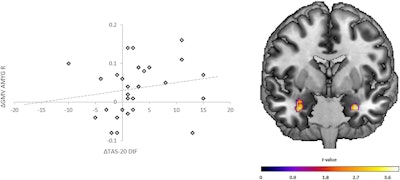

Gray-matter volume changes in the amygdala within patients and the association with improvements in alexithymia (Difficulty Identifying Feelings). (Left) Scatter plots depicting GMV changes (delta = t2-t1) within the cluster of the right amygdala (x = 32, y = −3, z = −27) on the y-axis correlated with changes (delta = t1-t2) in the Toronto Alexithymia Scale (TAS20) subscale Difficulty Identifying Feelings (DIF; rs = 0.321, p = 0.042) on the x-axis within the patient group. Line: regression slope. (Right) Coronal view (Montreal-Neurological-Institute coordinate y = 0) depicts the results of the paired t-tests (t1 vs. t2) in the patient group within the bilateral amygdala. Graphics, images, and caption courtesy of Translational Psychiatry via a Creative Commons License.Gray-matter volume changes in the amygdala within patients and the association with improvements in alexithymia (Difficulty Identifying Feelings). (Left) Scatter plots depicting GMV changes (delta = t2-t1) within the cluster of the right amygdala (x = 32, y = −3, z = −27) on the y-axis correlated with changes (delta = t1-t2) in the Toronto Alexithymia Scale (TAS20) subscale Difficulty Identifying Feelings (DIF; rs = 0.321, p = 0.042) on the x-axis within the patient group. Line: regression slope. (Right) Coronal view (Montreal-Neurological-Institute coordinate y = 0) depicts the results of the paired t-tests (t1 vs. t2) in the patient group within the bilateral amygdala. Graphics, images, and caption courtesy of Translational Psychiatry via a Creative Commons License.